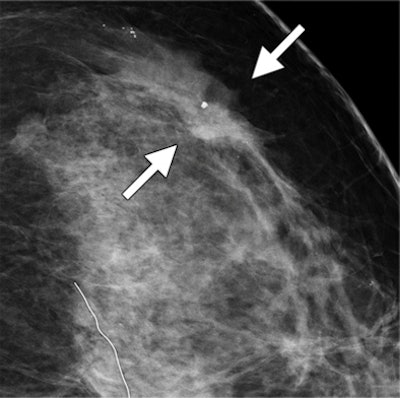

| Images show possible mass in a 54-year-old woman. Craniocaudal spot compression (above) and tomosynthesis (below) show biopsy-proved invasive ductal carcinoma (arrows). The spiculated mass margins are better shown with DBT than in the spot compression image. All images courtesy of RSNA. |